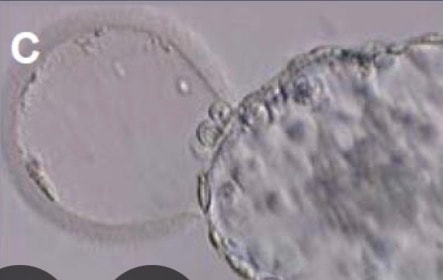

У вас 2аа. Ему нужно сначала вырасти выйти в хетчинг имплантация ещё 40ч потом начнёт хгч выделять ито тест уловит не сразу. Вы рано думаете плохо

Little Koldynia, я буду счастлива, если ошибаюсь , ну на 7 дпп должен хоть маленький хгч показать , если он имплантировался в принципе. Я нашла фото как выглядел он во время переноса, картинку нашла . Он вот так выходил из оболочки 🤷🏻♀️